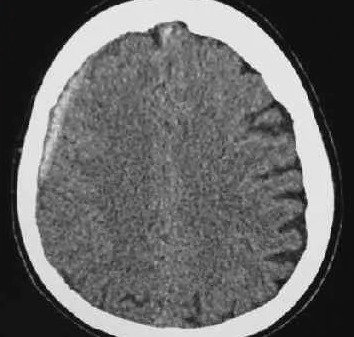

Субдуральная гематома диагностика